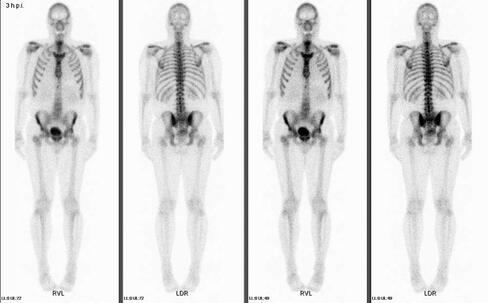

Mit der Methode ist die bildliche Darstellung des Knochenstoffwechsels in Knochen und Gelenken möglich. Es können entzündliche, degenerative sowie bösartige Veränderungen festgestellt werden, oftmals noch bevor sie im Röntgenbild zu erkennen sind. Ebenso lassen sich auch Verletzungen des Knochens, sowohl frische als auch monatelang zurückliegende, nachweisen, insbesondere wenn sie röntgenologisch nicht dargestellt werden können. Ein unauffälliges Knochenszintigramm schließt eine Erkrankung des Knochens weitgehend aus.

Zu Beginn der Untersuchung wird Ihnen eine geringe Menge einer radioaktiven Substanz (Tc99m markierte Phosphonatverbindung) in eine Vene gespritzt. Diese Substanz beteiligt sich am Knochenstoffwechsel und reichert sich insbesondere an der Knochenoberfläche vorübergehend an. Zur bildlichen Darstellung werden Aufnahmen mit einer Gammakamera ca. 3 Stunden nach der Injektion durchgeführt, Dauer ca.1 Stunde, in der Regel liegend auf dem Rücken. Sie erleichtern uns den Ablauf, wenn Sie am Tag der Untersuchung auf metallische Gegenstände am Körper oder in der Kleidung (z.B. Schmuck, Schüsselbund) verzichten.

Bei bestimmten

Fragestellungen, insbesondere zur Beurteilung möglicher entzündlicher

Veränderungen, wird zusätzlich die Weichteildurchblutung untersucht und

dazu ergänzende sogenannte Frühaufnahmen erstellt. Bei dieser

Mehrphasen-Szintigraphie erhalten Sie die Spritze, während Sie unter der

Kamera liegen oder sitzen und die Frühaufnahmen werden gleich nach der

Injektion durchgeführt.